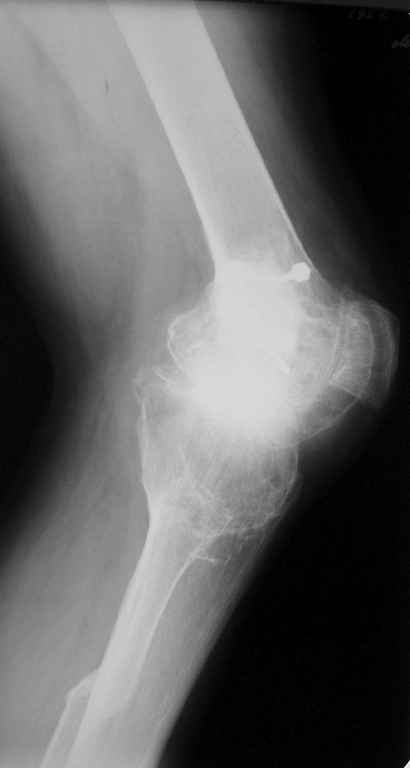

Пациент 59 лет, в 1982 году по поводу остеобластокластомы была выполнена частичная резекция проксимального отдела бедра с пластикой дефекта костно-хрящевым трансплантатом (моноблок)с фиксацией металлическими стяжками. В последующем по поводу деформирующего артроза выполнена корригирущая остеотомия большеберцовой кости. Исход представлен на рентгенограмме. В настоящий момент пациента беспокоят боли в коленном суставе, деформация, и ограничение движений. Варусная деформация коленного сустава 20, движения сгибание 115, разгибание 150, ходит с тростью, выраженная хромота, работа не связана с физическими нагрузками. Правый коленный сустав без патологии. Уважаемые коллеги просим высказать своё мнение - артродез коленного сустава или эндопротезирование.